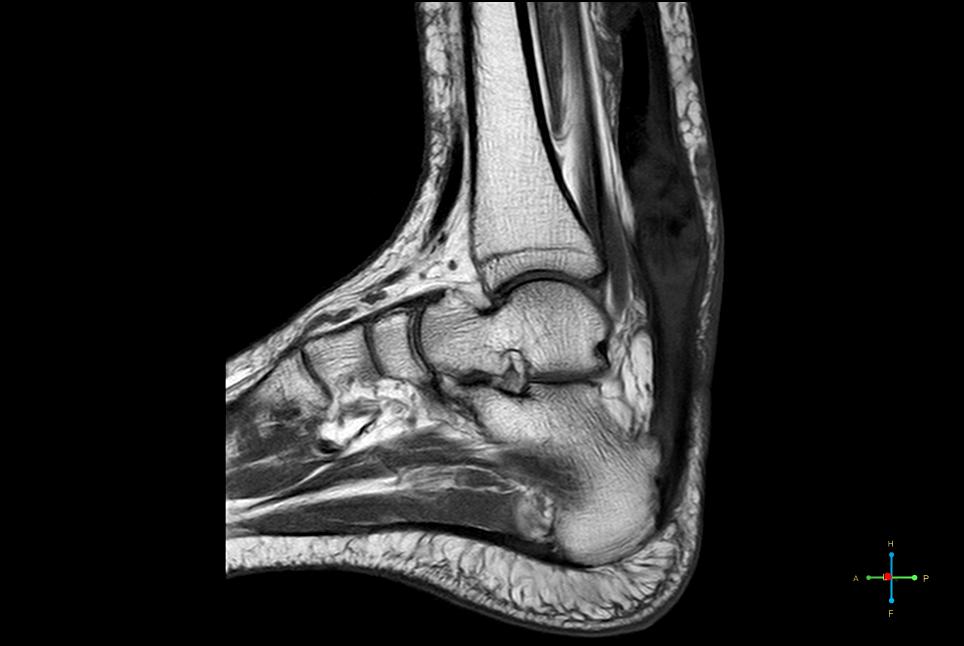

From www.mri.melbourne

MRI Achilles Tendon Melbourne Radiology Plantar Xanthoma Mri Some of the more common causes include achilles tendinosis, haglund phenomenon, and plantar fasciitis. This review article exemplifies simple and systematic guidelines for imaging assessment of plantar fascia disorders, with a focus on key findings detectable on plain radiography, ultrasound and magnetic resonance imaging (mri). Thickening and signal changes in the pf as well as oedema of adjacent soft tissues. Plantar Xanthoma Mri.